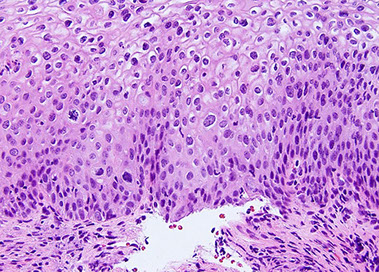

Histo: suprabasilar / intraepidermal blister and acantholysis

- "tombstones" - basal keratinocytes that remain attached to BM

IF: IgG and C3 deposition bwt cells in epidermis in fishnet or "chicken-wire" pattern

A) Pemphigus vulgaris, B) Pemphigus follicularis with suprabasal epidermal cleavage